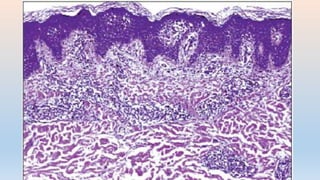

DERMATITIS FOTOTOXICA

• PREVALENCIA ALTA,MAS EN ANCIANOS

• REACCION A LA PRIMERA EXPOSICION

• LATENCIA DE MINUTOS A HORAS

• DOSIS REQUERIDA GRANDE

• ESPECTRO DE ACCION ESTRECHO (UVA1)

• NO HAY TENDENCIA A EXTENDERSE

• DAÑO CELULAR DIRECTO

• QUERATINOCITOS NECROTICOS

CARIOLISIS, CARIOREXIS

PICNIOSIS